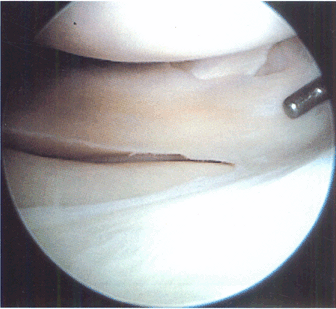

Figure 85.2.

Incomplete tear of the superior surface of the lateral meniscus associated with an anterior cruciate ligament tear. (This figure is printed in black and white as Figure 2 of Chapter 85.) |